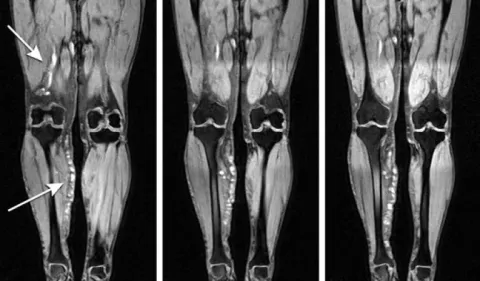

На объемных изображениях, полученных с помощью МРТ конечности, хорошо видны даже небольшие по размеру тромбы, локализованные в сосудах нижних конечностей и глубоких вен, жизнеобеспечивающих органах и головном мозге. Этот инструментальный метод дает возможность получить визуальное представление о состоянии участков кровеносной системы и проанализировать влияние на них окружающих тканей.

Вид тромбов на снимках МРТ

Результатом сканирования является целая серия снимков с послойным изображением отдельной зоны системы кровоснабжения. При таком подходе получается фото срезов с шагом от 1 мм. Поэтому визуализируются сгустки даже очень малых размеров.

В процессе сканирования о наличии тромбов в кровеносном русле судят по изменению сигнала. При эмболии сосудов интенсивность сигнала нарастает на участках, которые находятся выше окклюзии.

Если внимательно рассмотреть снимок томограммы, то тромб будет иметь округлую форму с утолщением в месте крепления его к стенке сосуда. Но если полностью перекрыт кровоток, то это считается полной окклюзией.